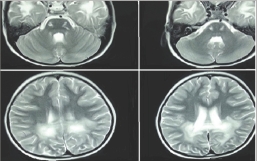

Figure 1: MR T2 images show corticospianl tracts involvement that spare cerebellum (Upper row), hyper intensities in posterior white matter with different zones characteristic for ALD. (Lower row)

MRI at the age of 5 revealed severe signal changes in per ventricular white matter of bilateral posterior occipital regions. There was no neocortical dysplasia or atrophy, and the cerebellum was normal. However, splenuim of corpus collosom and corticospinal tracts were affected (Figure 1). Different zones (ALD- like) were clearly differentiated on T2 MR Image. Second MRI at the age of 7 revealed extensive white matter involvement along with generalized atrophy. MRS demonstrated a choline rise in respect to NAA (N-Acetyl Aspartic Acid) compatible with leukodystrophy pattern.